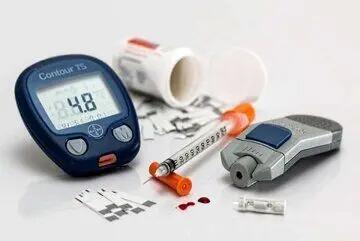

برای جلوگیری از دیابت بارداری چه کار کنیم ؟ ؛ راهکارهای جلوگیری از دیابت بارداری | دیابت بارداری از کی شروع می شود ؟

عواقب دیابت بارداری کنترل نشده بسیار جدی است، اما این شرایط به سادگی و تا زمانی که زود تشخیص داده شود، به خوبی قابل کنترل و درمان است و برای مادر و جنین آسیبی به همراه ندارد.